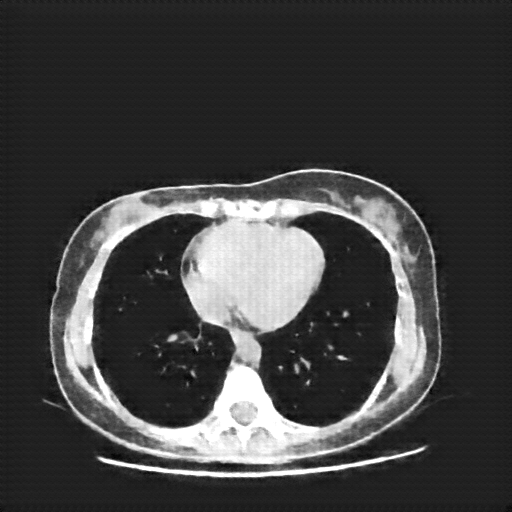

Original VENOUS CT scan

Full window (WL 1023.5, WW 4095 β†’ Low βˆ’1024, High +3071)

Lung window (WL -600, WW 1500 β†’ Low βˆ’1350, High +150)

Mediastinum window (WL 40, WW 400 β†’ Low βˆ’160, High +240)